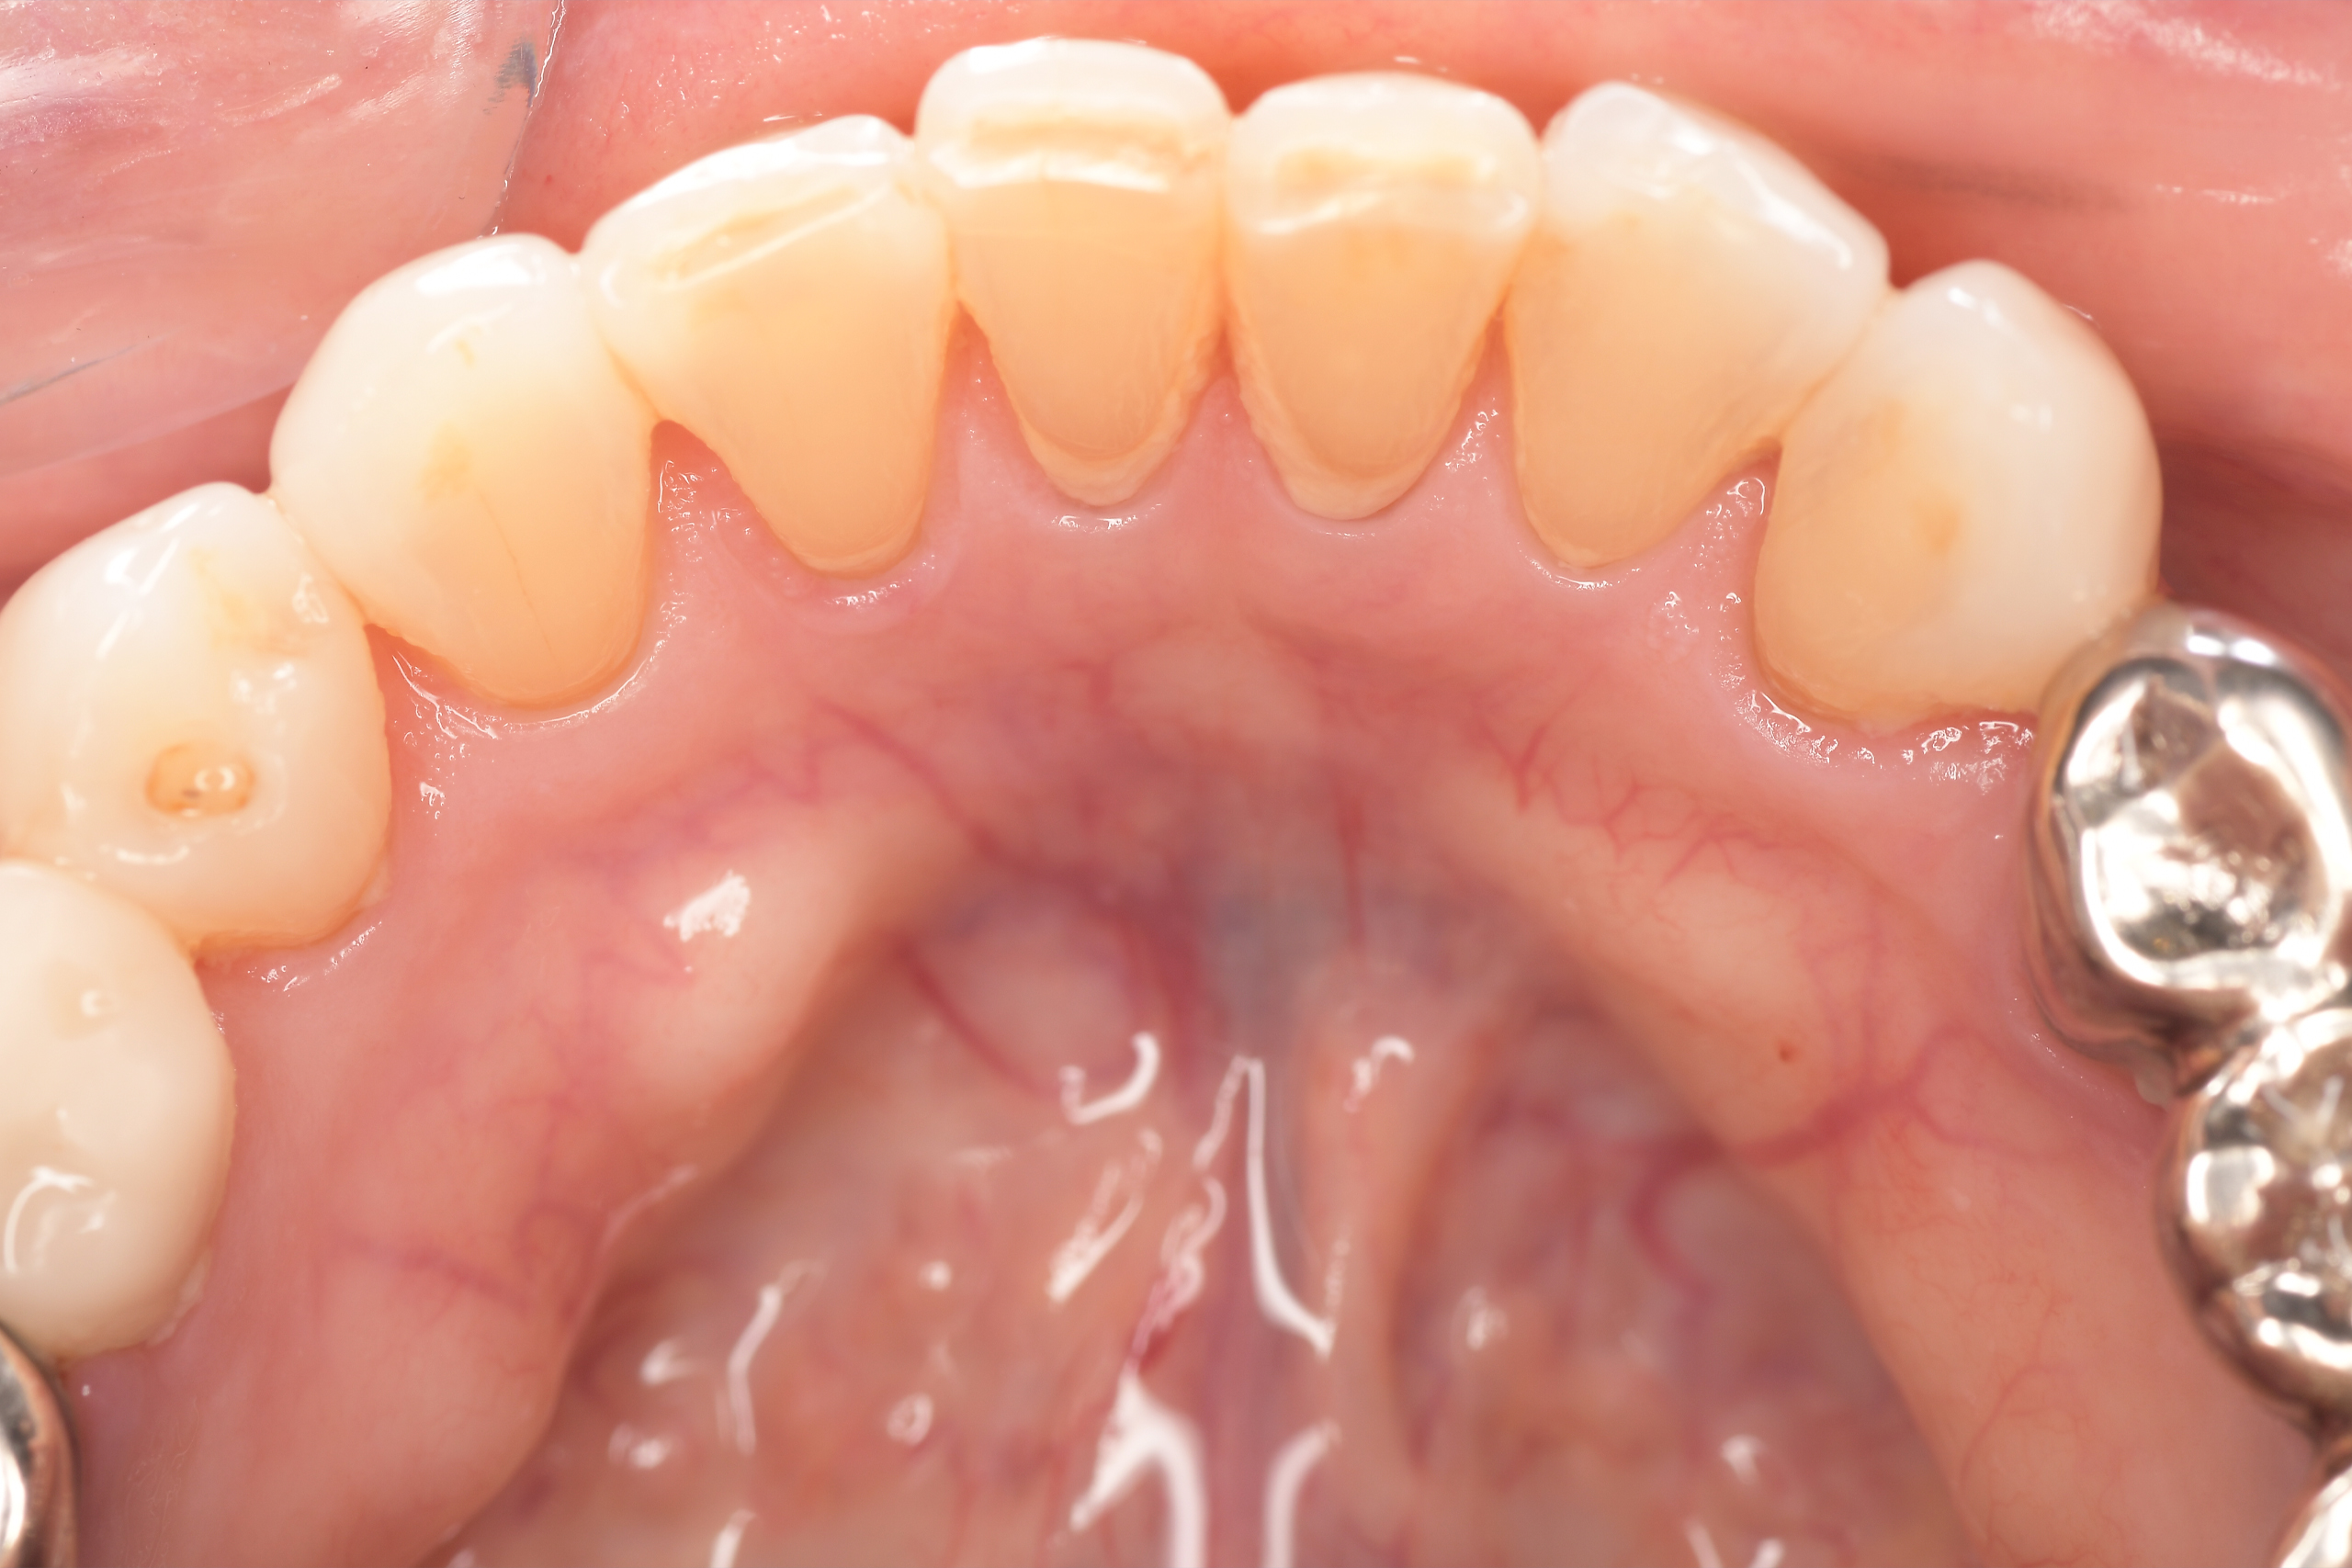

CASE 7

Before

After

基本情報

| 年齢・性別 | 48歳・男性 |

|---|---|

| 主訴 | 定期検診 |

| 治療内容 | スケーリング |

| 治療期間 | 60分 |

| 治療費 | 1,500円(保険診療) |

| リスク・副作用 | 知覚過敏、出血 |

| 治療方針 | まず歯肉縁上歯石を除去して、スッキリとした感覚や滑らかな舌ざわりを実感してもらいました。この状態を保てるように歯磨きの仕方や、歯周病についてお話ししました。 今後は歯肉縁下歯石を除去して、歯周病治療を行っていきます。 |

| 担当者所見 | 久しぶりの歯科医院への受診でした。 治療に慣れていないため、少しずつ歯石を除去していきました。 |